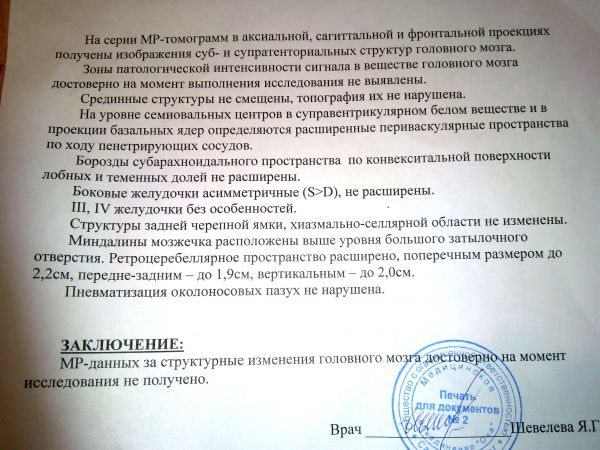

МРТ головного мозга: Расшифровка снимков и Интерпретация

Раздел: Визуальные уроки